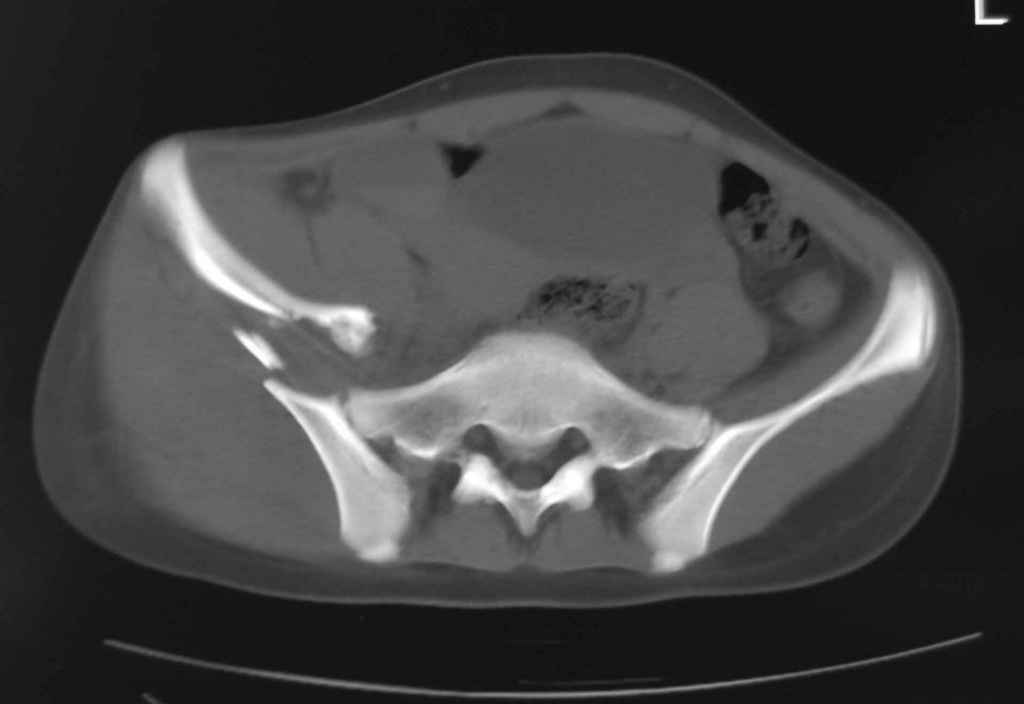

Принципиально важно видеть все срезы КТ через вертлугу, так как тактика лечения будет в первую очередь обусловлена характером перелома ветрлужной впадины, во вторую - вертикальным смещением таза ( где варианты - от банального скелетного вытяжения до ВЧКО или накостного остеосинтеза - в основном зависит от пресловутой "позиции кафедры")

Уважаемый Алексей, на представленных Вами снимках имеется вертикально-нестабильное повреждение тазового кольца без повреждения вертлужной впадины. Учитывая это, а так же растущий возраст ребенка я бы выбрал аппарат внешней фиксации в виде кольцевой опоры, т.к. не смотря на оскольчатый перелом крыла в переднем отделе можно ввести минимум 2 стержня + 1-2 надвертлужно. Этого будет достаточно чтобы "зацепится", выполнить репозицию и дальнейшую фиксацию. Перелом шейки по моему лучше прооперировать 3 канюлированными винтами по АО.